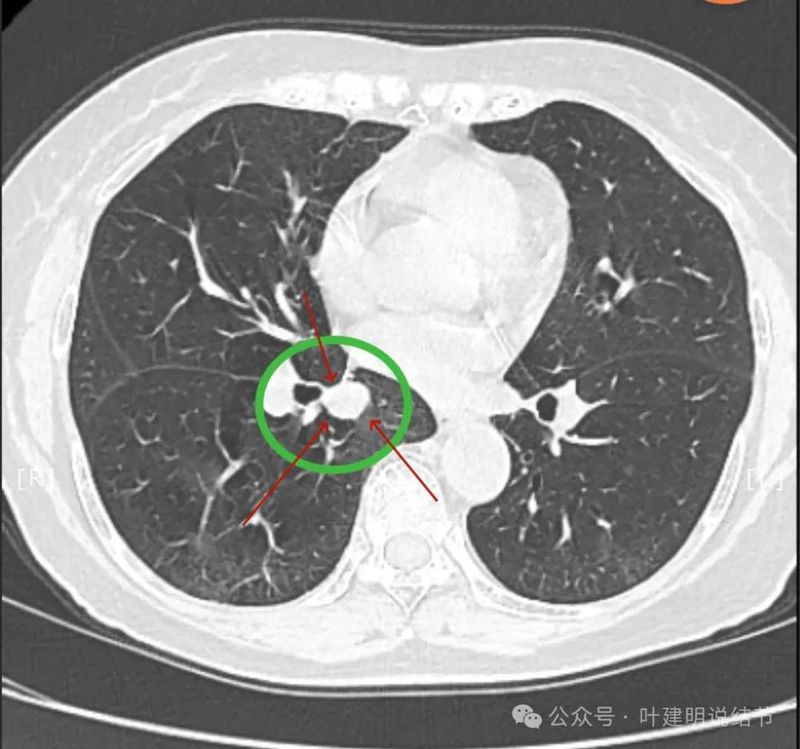

实性密度,边缘光滑,与背段支气管亚段贴着。

天蓝色箭头示病灶与支气管之间有缝隙,但贴的较近;黄色箭头示支气管管腔;红色箭头示病灶,边缘光滑。

支气管受压,但无明显破坏;与支气管之间紧贴位有的位置仍有缝隙;病灶边缘光滑。

病灶密度较为均匀,对支气管是压迫后移位。表面光滑。

似乎有血管穿过。

边缘光滑,没有毛刺,膨胀性生长。

表面光滑,内部密度较均匀,边界清楚,膨胀性长。

没有侵犯邻近支气管。

边缘光滑,分叶不明显。